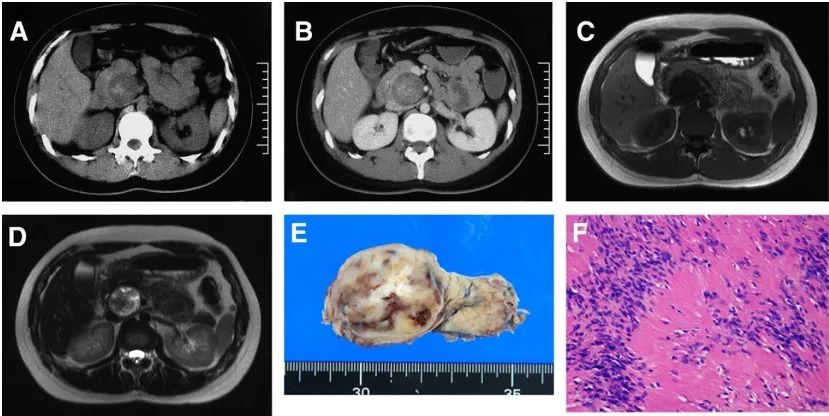

一名 32 岁的日本女性,主诉为背痛。入院时,其既往病史、体格检查和实验室值,包括肿瘤标志物,均无显著差异。

图 4(A-F)

超声检查显示在胰腺头部有一个低回声肿瘤,直径 4.0 厘米。对比前 CT 显示,该肿瘤是一个界限清楚的低密度病变,具有高密度成分(图 a)。对比注射后,病变显示不均匀的低密度,中心有高密度成分(图 B)。磁共振成像显示肿瘤在 T1 加权序列上呈均匀低信号(图 C),在 T2 加权序列上呈非均匀高信号和低信号区域(图 D)。这些影像学表现提示存在不同阶段的出血和退行性改变,包括囊肿的形成。该肿瘤,根据临床表现和影像学特征,被怀疑为一种实性-假性乳头状肿瘤(SPN)。

行胰十二指肠切除术。切除标本的切面检查显示一个坚硬、白色、3.5 cm 边界清楚的包裹实体瘤,局灶性退行性改变:囊肿形成、坏死和出血(图 E)。镜下,病变被厚厚的纤维胶原包膜和正常的胰腺实质所包围。病变显示出不同程度的细胞数量。细胞区域由梭形细胞组成,细胞核细长,呈束状排列(图 F)。低细胞区域显示囊肿形成、出血、含铁血黄素的巨噬细胞和水肿的间质。细胞成分中的梭形细胞群中 S100 蛋白强烈阳性,细胞角蛋白、上皮膜抗原、平滑肌肌动蛋白、结蛋白、神经丝、CD34 和 CD117 呈阴性(c-kit)。根据这些发现,该肿瘤被诊断为胰腺神经鞘瘤。